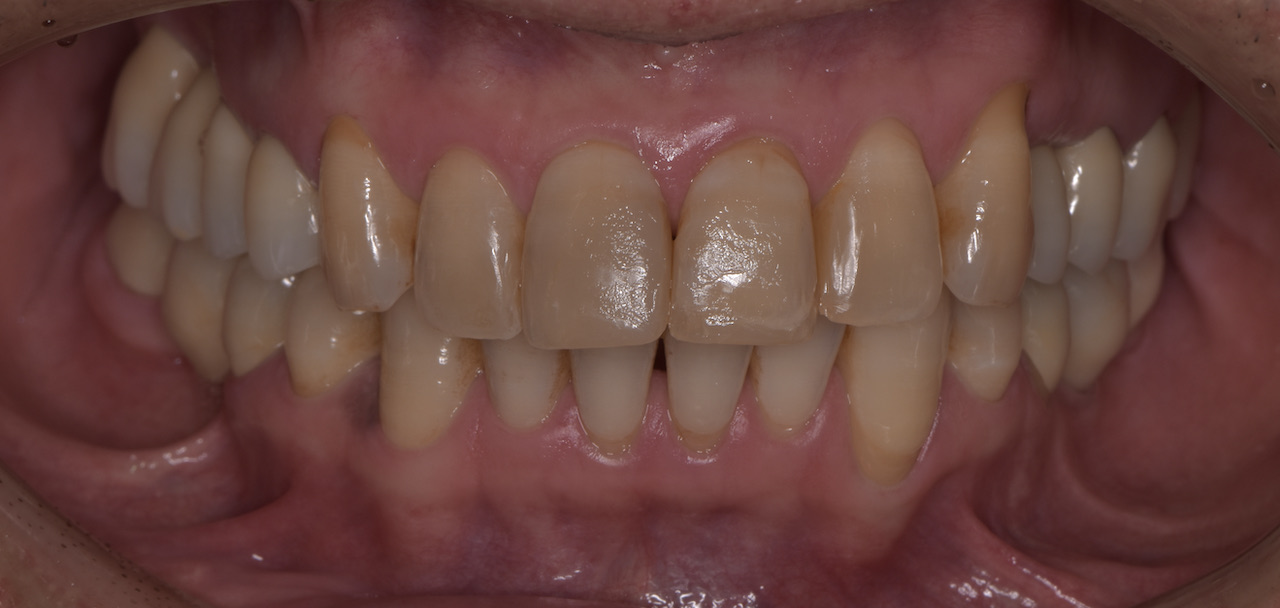

全顎的に複数の治療部位で、インプラント・ブリッジ・ダイレクトボンディング・セラミッククラウンなど、適切な治療方法を組み合わせて包括的な治療を進めました。

治療を終えた「T-scan」による咬合調整後の患者さんの感想を伺うと「とても良く咬め、インプラントが入っていても全く違和感を感じない」という事でした。このようにデジタルで計測される客観的なデータと患者さんこそが一番感じるご自身からの体の声を一体化させる治療が大切です。